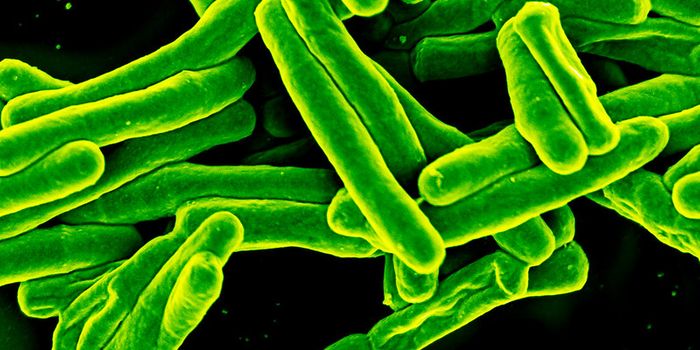

AUG 26, 2024Clinical & Molecular DXA colorized scanning electron micrograph depicts a Kupffer cell. / Credit: Thomas Deerinck, National Center for Microsco ...